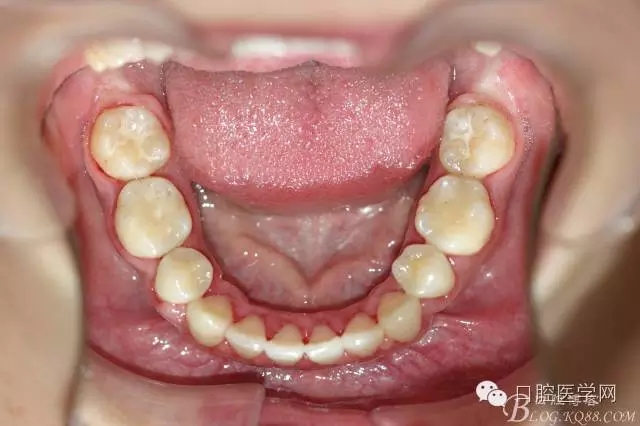

正畸查:替牙合。第一恒磨牙中性合。上牙弓尖圓型下牙弓方圓型。前牙覆合3度覆蓋7.5mm。下前牙咬到上舌側(cè)牙齦。上頜擁擠4.0mm,下頜擁擠

3.0mm。上頜稍前突下頜后縮,上下唇前突,上前牙覆蓋下唇,下唇外翻。面下三分之一過(guò)短,頦唇溝明顯,開(kāi)唇露齒,頦饜窩明顯。顳下頜關(guān)節(jié)開(kāi)閉口無(wú)彈響,無(wú)壓痛,開(kāi)口型開(kāi)口度正常。

正畸前照片: